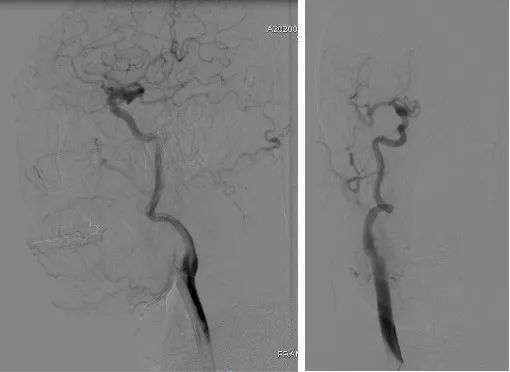

经右侧股动脉鞘,黑泥鳅导丝带领导引导管(Codman 6F Envoy DA)到达右侧颈内动脉岩段,微导丝(Synchro--14 0.014 in*200 cm)带领支架微导管(Excelsior SL--10)到达右侧大脑中动脉M2段,退出微导丝。微导丝带领弹簧圈微导管(Echelon10)到达右侧M1远端分叉处动脉瘤内,退出微导丝。经弹簧圈微导管填入弹簧圈(Codman 3 mm*4 cm)经支架微导管输送支架(Neuroform Atlas 3.0 mm*15 mm)并释放在M2段至M段中部,完全覆盖动脉瘤颈。继续经弹簧圈微导管依次填入弹簧圈数枚,间断造影确保右侧大脑中动脉及远端血流通畅。右侧颈内动脉造影确认:动脉瘤致密填塞,载瘤动脉通畅,手术结束。有侧股动脉穿刺处用血管封堵器封堵,并压迫器持续压迫。术后患者麻醉清醒,拔除气管插管,呼唤应答,对答切题,言语清楚,四肢肌力肌张力正常。安返病房。

患者在全麻下、多参数监护仪监测下行前交通动脉瘤经右侧颈内动脉支架辅助下栓塞术。全麻后,常规消毒销巾,采用改良seldinger技术穿刺右侧股动脉或功,置入6F动脉鞘。黑泥鳅导丝及多功能导管带领6F MPD导管达到右侧颈内动脉岩段,行造影见∶前交通动脉瘤,瘤体3.5 mm*5.1 mm。在路图引导下,徵导丝(Synchro 0.014 in*200 cm)带领弹支架微导管(SL-10)到右侧大脑前动脉A2段,退出微导丝。微导丝(Synchro 0.014 in*200 cm)带领弹簧圈微导管(eV3 Echelon-10)到达前交通动脉瘤体内,退出微导丝。经弹簧圈微导管填入首枚弹簧圈(Codman COMPLEX XTRASOFT3 mm*6 cm)成篮良好,在路图引导下在支架管内输送支架(Neuroform Atlas 3.0 mm*21 mm)并释放完全覆盖动脉瘤颈,造影可见支架打开良好解脱首枚弹备圈,沿弹簧圈导管继续填入弹簧圈(可见护理记录单)间断造影确保双侧大脑前动脉血流通畅。右侧颈内动脉造影确认∶前交通动脉瘤填塞致密,双侧大应前动脉血流通畅。手术结束。右侧股动脉鞘处用血管封堵器(Coxrds Exoseal 6F)封堵,并压迫器持续压迫。木后患者清醒。